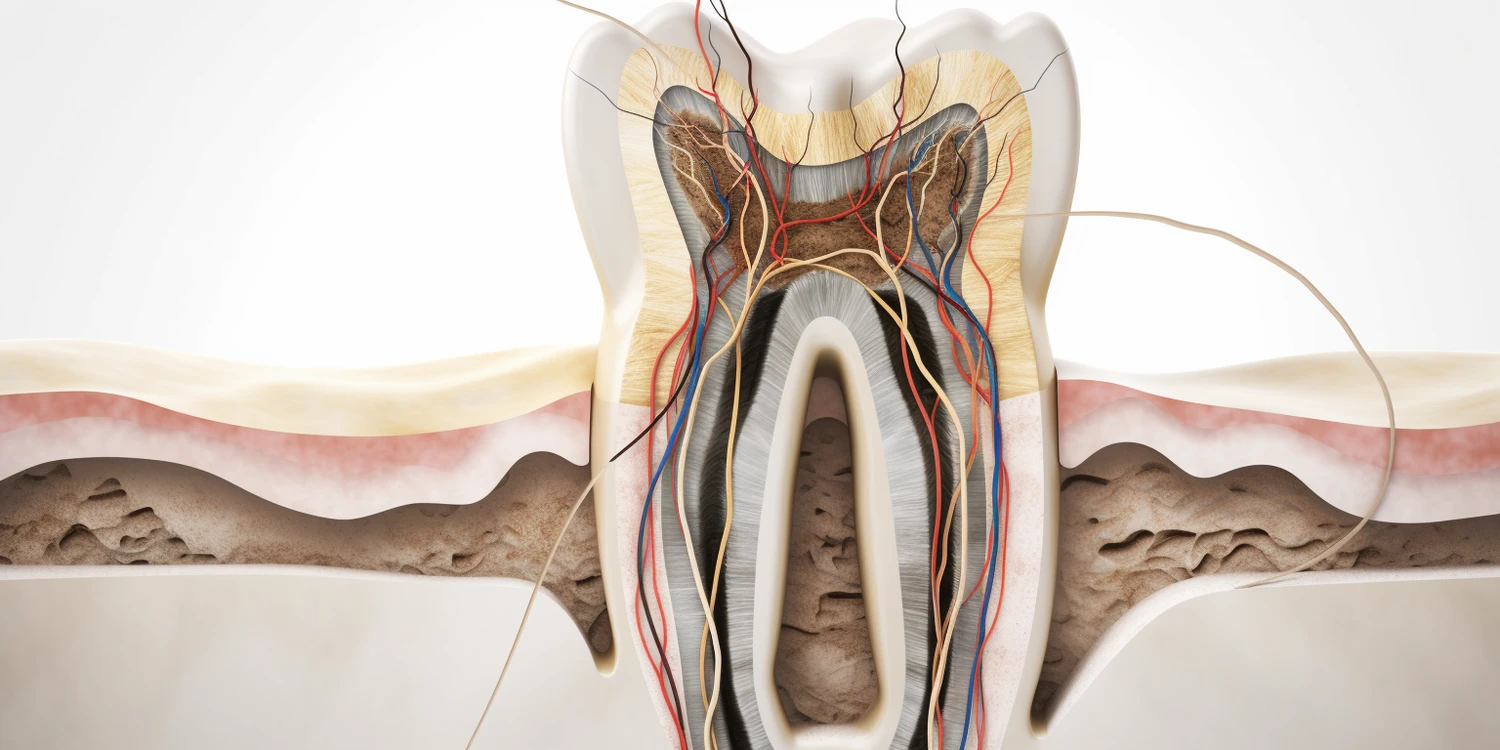

Leczenie kanałowe, znane również jako endodoncja, to procedura stomatologiczna mająca na celu uratowanie zainfekowanego lub uszkodzonego zęba. W trakcie tego zabiegu dentysta usuwa miazgę zęba, która może być źródłem bólu oraz stanu zapalnego. Miazga to tkanka zawierająca naczynia krwionośne oraz nerwy, a jej usunięcie pozwala na oczyszczenie wnętrza zęba. Po usunięciu miazgi dentysta dokładnie dezynfekuje kanały korzeniowe, aby usunąć wszelkie bakterie oraz resztki tkankowe. Następnie kanały są wypełniane specjalnym materiałem, co zapobiega dalszym infekcjom. Leczenie kanałowe jest często jedynym sposobem na uratowanie zęba przed ekstrakcją, a jego celem jest przywrócenie pełnej funkcji zęba oraz eliminacja bólu. Warto zaznaczyć, że pomimo skomplikowanej procedury, leczenie kanałowe jest zazwyczaj bezbolesne dzięki zastosowaniu znieczulenia miejscowego.

Proces leczenia kanałowego składa się z kilku kluczowych etapów, które są starannie zaplanowane przez dentystę. Pierwszym krokiem jest dokładna diagnoza, która obejmuje badanie kliniczne oraz zdjęcia rentgenowskie mające na celu ocenę stanu zęba i otaczających tkanek. Po ustaleniu diagnozy pacjent otrzymuje znieczulenie miejscowe, aby zapewnić komfort podczas zabiegu. Następnie dentysta przystępuje do otwarcia korony zęba w celu uzyskania dostępu do miazgi i kanałów korzeniowych. Kolejnym krokiem jest usunięcie chorej miazgi oraz dokładne oczyszczenie wnętrza zęba za pomocą specjalistycznych narzędzi endodontycznych. Po zakończeniu oczyszczania dentysta wypełnia kanały materiałem uszczelniającym i zamyka otwór w koronie zęba. W niektórych przypadkach konieczne może być wykonanie dodatkowej odbudowy zęba za pomocą korony protetycznej.